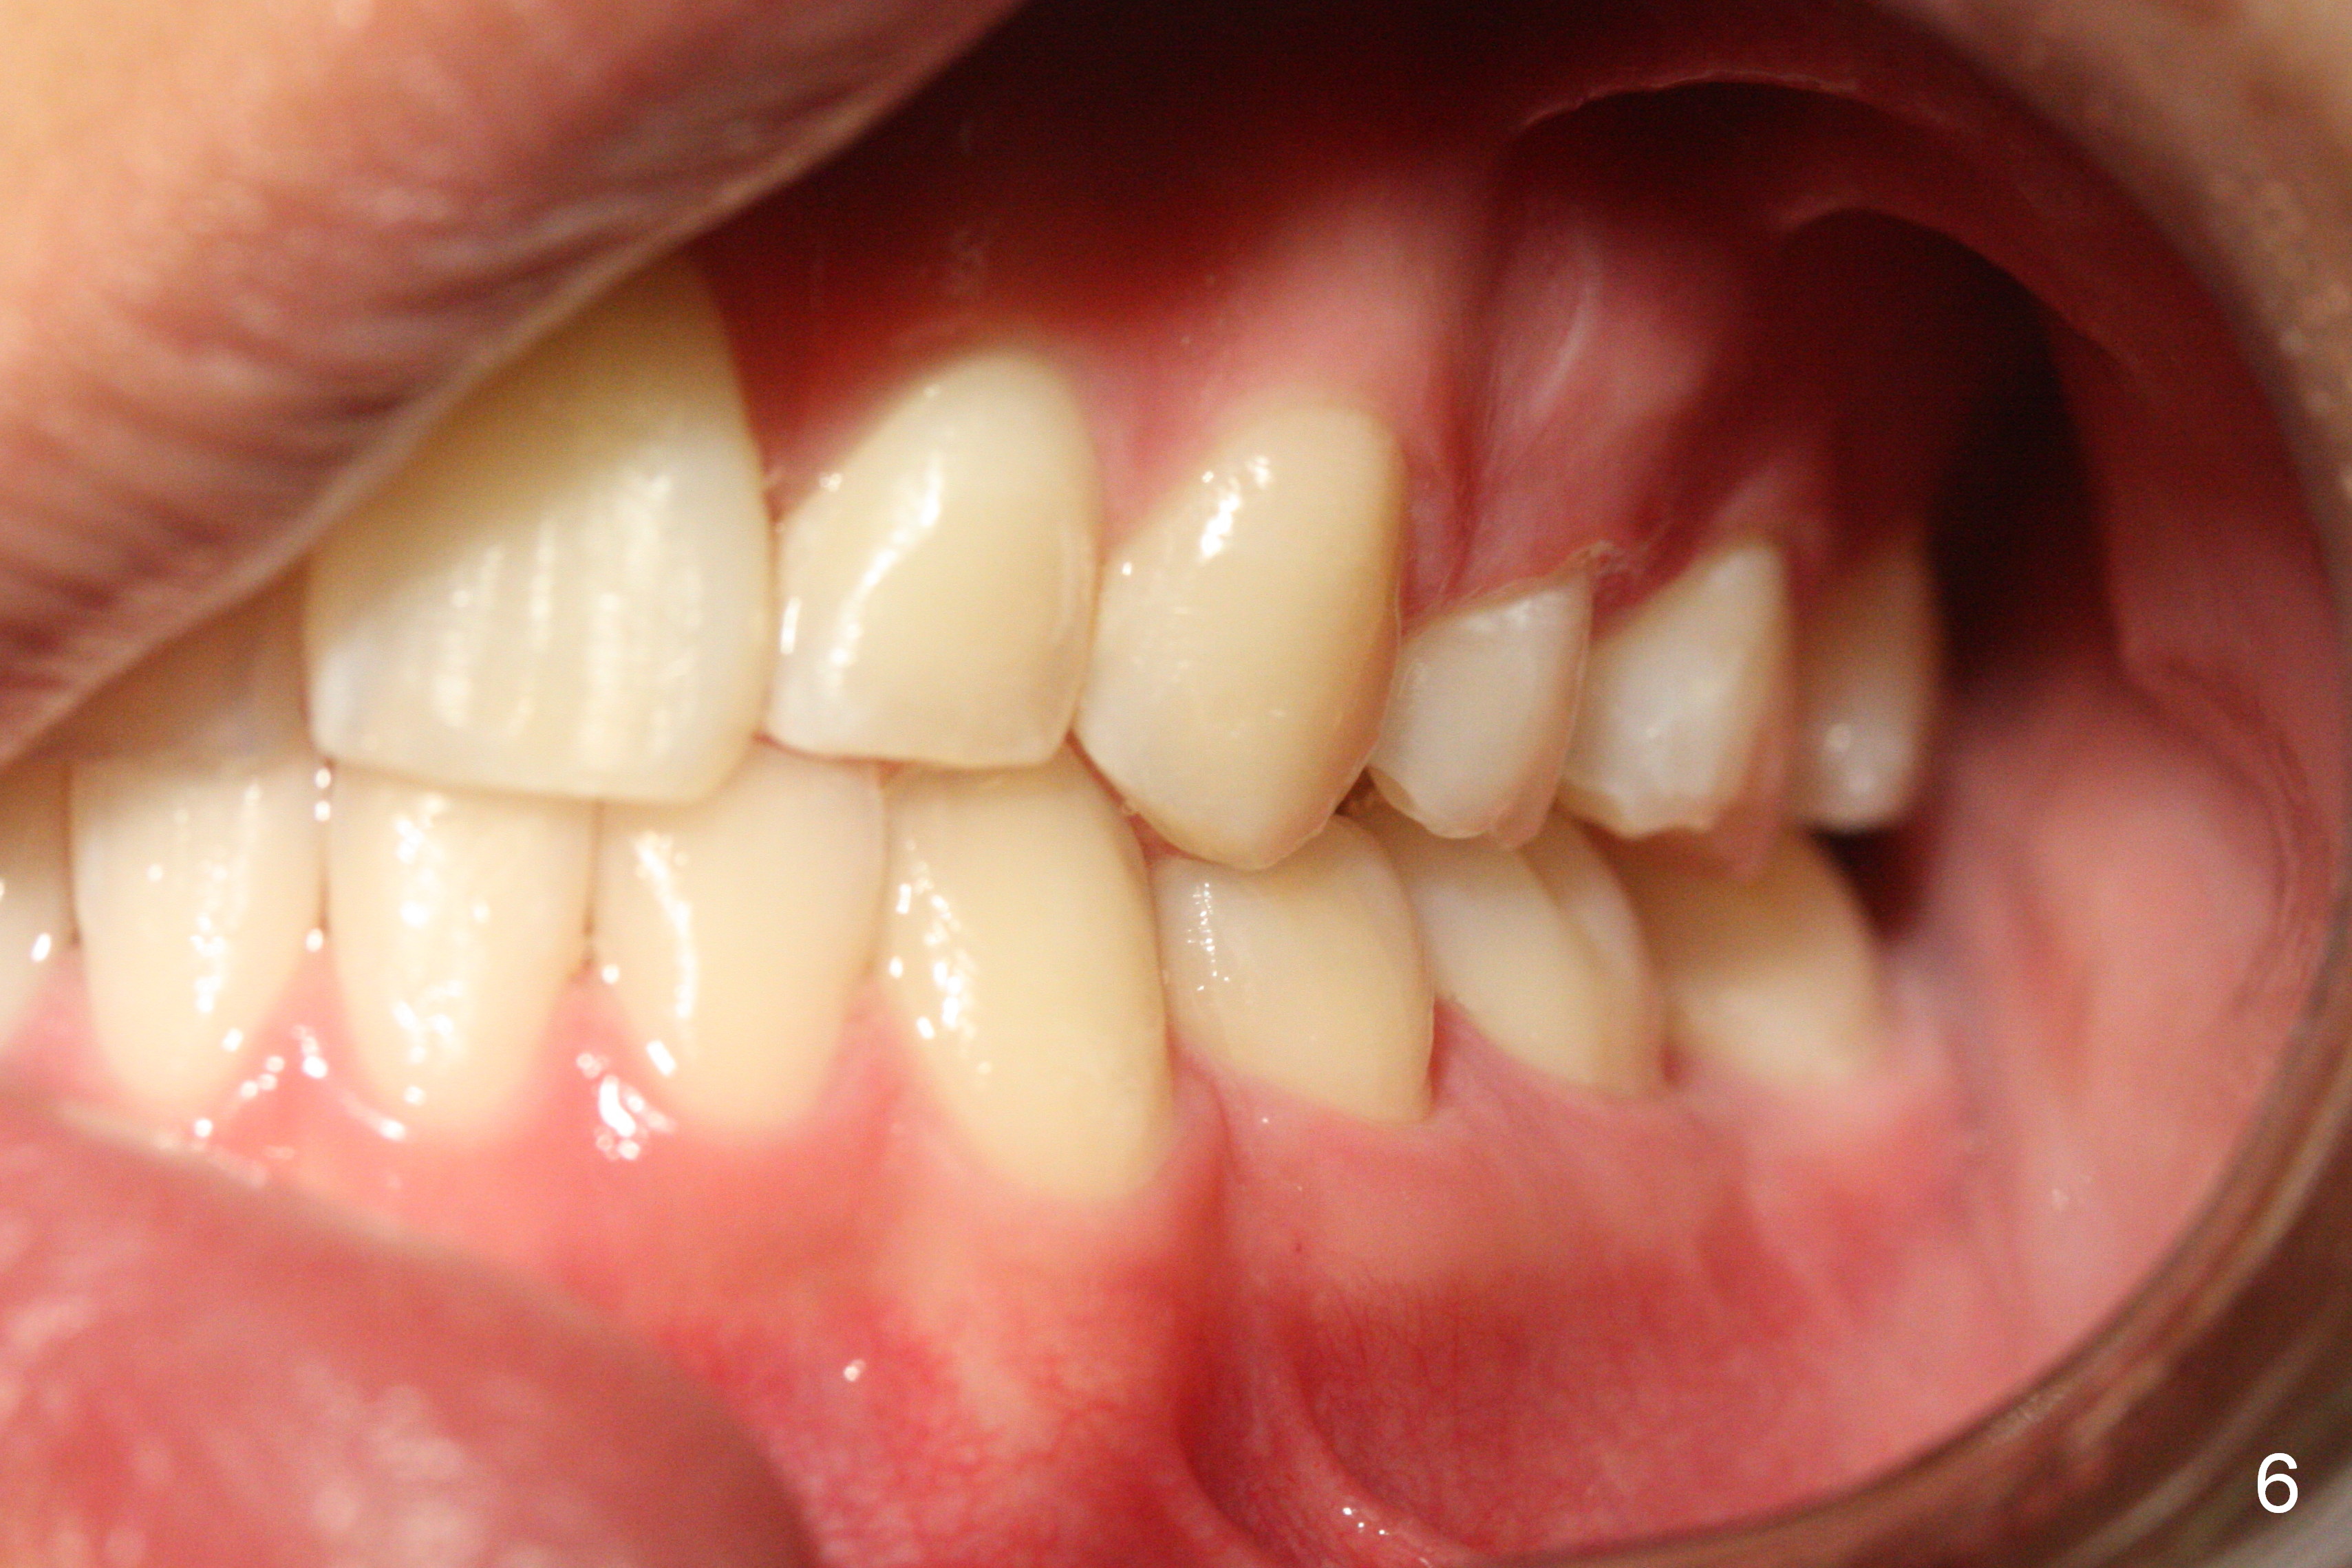

When taking photos for the lateral view of the occlusion (Fig.3, retract the corner mouth as back as possible using proper sized cheek retractors (single or double, child or adult) or a mouth mirror. The focus should be on the posterior teeth, showing interdigitation. That is move the camera to the side of the face.